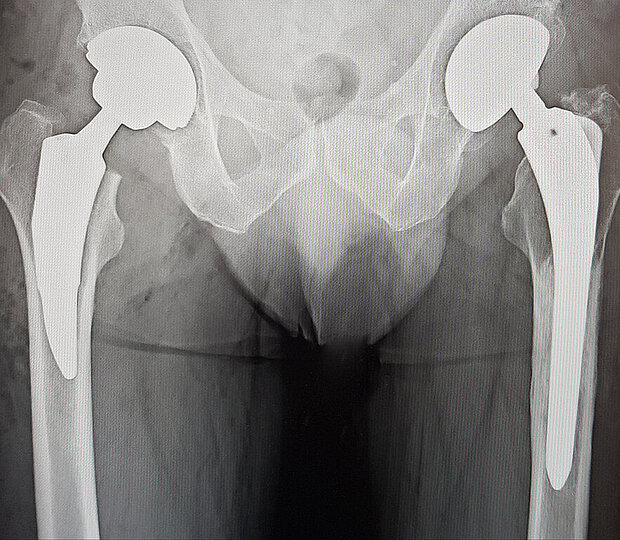

Die Hüftgelenksprothetik - also ein Gelenkersatz im Bereich des Hüftgelenks - kann bei einer starken Arthrose oder einer hüftgelenksnahen Fraktur zum Einsatz kommen.

Sie tritt vorwiegend im mittleren bis höheren Lebensalter auf, kann aber auch schon bei unter vierzigjährigen Patientinnen und Patienten in Erscheinung treten und zu starken Beschwerden führen. Die Beschwerden äußern sich in Bewegungs- und Belastungsschmerzen, dann auch Ruhe- und nächtliche Schmerzen. Dies meist in Begleitung von mehr oder wenig stark ausgeprägter Bewegungseinschränkung der betroffenen Hüfte. Die Coxarthrose kann einseitig oder auf beiden Seiten auftreten. Im Gesundheitszentrum Tuttlingen werden jährlich circa 400 Hüft-Total-Endoprothesen implantiert. In den allermeisten Fällen werden die künstlichen Hüftgelenke zementfrei eingebaut. Außerdem verwenden wir bei den Hüftprothesen häufig schonende Kurzschaftprothesen.